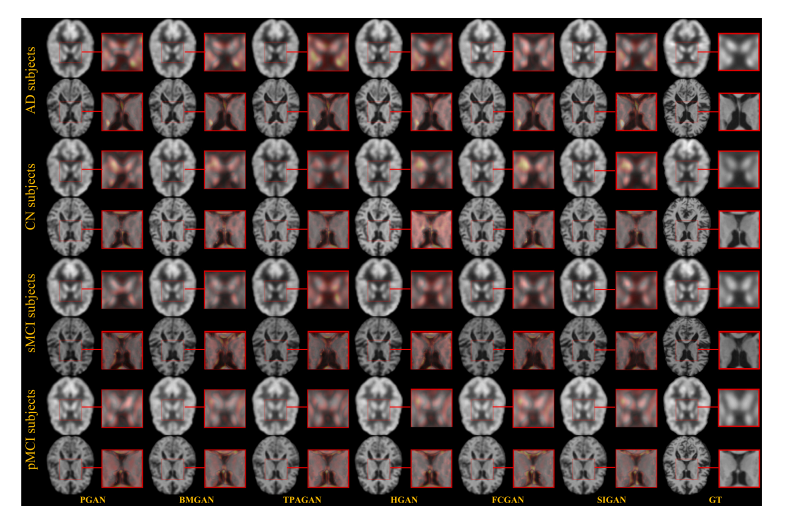

Fig. 6. For MRI and PET imputation tasks, visualization results of all competing methods on some representative cases in the ADNI-1 training and ADNI-2 testing scenario. GTdenotes the ground-truth.

图 6.在 MRI 和 PET 填充任务中,各对比方法在 ADNI-1 训练集和 ADNI-2 测试集部分代表性病例上的可视化结果。GT 表示真实影像(Ground-Truth)。

Fig. 7. For MRI and PET imputation tasks, visualization results of all competing methods on some representative cases in the ADNI-2 training and ADNI-1 testing scenario. GTdenotes the ground-truth

图 7.在 MRI 和 PET 填充任务中,各对比方法在 ADNI-2 训练集和 ADNI-1 测试集 部分代表性病例上的可视化结果。GT 表示真实影像(Ground-Truth)。